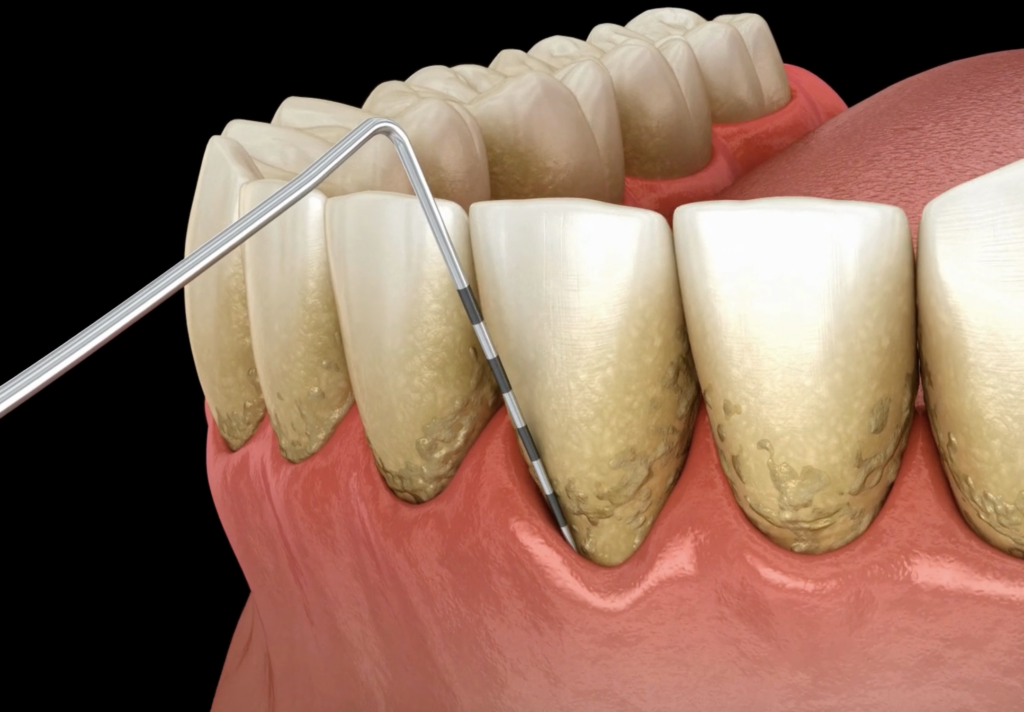

歯周病の検査では、動画でご覧いただいたように、プローブという、目盛り(物差しのような)のついた器具を使って測定を行います。

これは、歯と歯ぐきの境目にある溝(歯周病で深くなれば歯周ポケットになる)の深さを測かり、歯ぐきの状態を知る大切な検査です。

- 健康な歯ぐき: 歯と歯ぐきの境目の溝の深さは、通常2mm以下です。

- 炎症がある歯ぐき: 3mm以上の場合、歯ぐきに炎症が起きているサインです。歯肉炎や歯周病の進行度に応じて溝はさらに深くなっていきます。

つまり、この検査の数値を見ることで、あなたの歯ぐきが今どのような状態にあるのか、そして炎症や歯周病がどの程度進んでいるのかがレントゲンなどと合わせてよりわかります。

🔍 歯周組織検査

専用の器具(プローブ)を使って、歯周ポケットの深さや、歯ぐきからの出血・膿が出るかの有無、歯の動揺などを一本一本細かく測定します。このデータが、現在の歯周病の進行度を把握するための基本となります。最初にさせていただく基本検査、次にもっと詳しく精密検査をこのプローブを使って計測していきます。